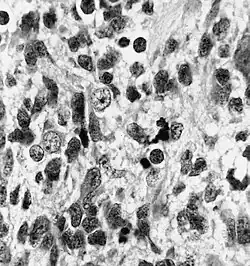

Histopathology of medulloepithelioma showing characteristic neural tube like strands. | |

Histologically, medulloepithelioma resemble a primitive neural tube and with neuronal, glial and mesenchymal elements.[8][9] Flexner-Wintersteiner rosettes may also be observed.[10]

Immunohistochemically, neural tube-like structures are vimentin positive in the majority of medulloepitheliomas.[11] Poorly differentiated medulloepitheliomas are vimentin negative.